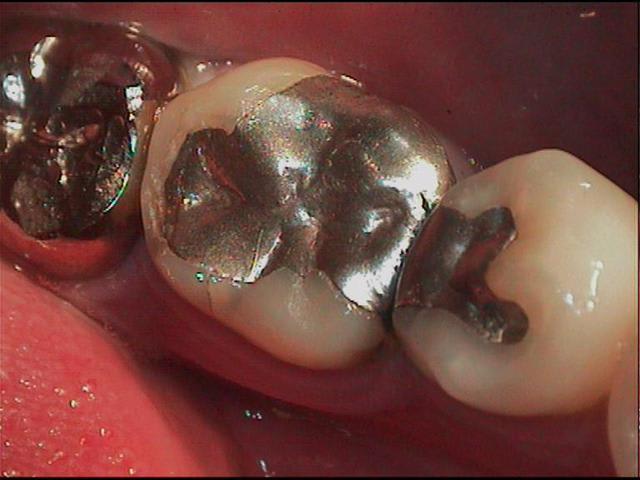

bon je t'aide, ils ont 20ans et j'ai pas repoli pour la photo (du reste déjà postées il y a un bail)

24ans après verif dossier

dents vivantes, pas de tenon dentinaire par contre (je suppose qu'entre les 6ans qui séparent les deux cas on avait décidé que c'était iatrogène)

Fissure au lingual...

sauf que j'ai les 2 cotés de la photos;) qd ça lachera c'est sur 2 mm en haut de la cuspide qu'il faudra de tout e façon recouvrir .

b/ la felure est là au moins depuis 2006 et n'a pas bougé.

C: si c'etait sur un inlay ceram, est ce que vous demonteriez pour refaire?